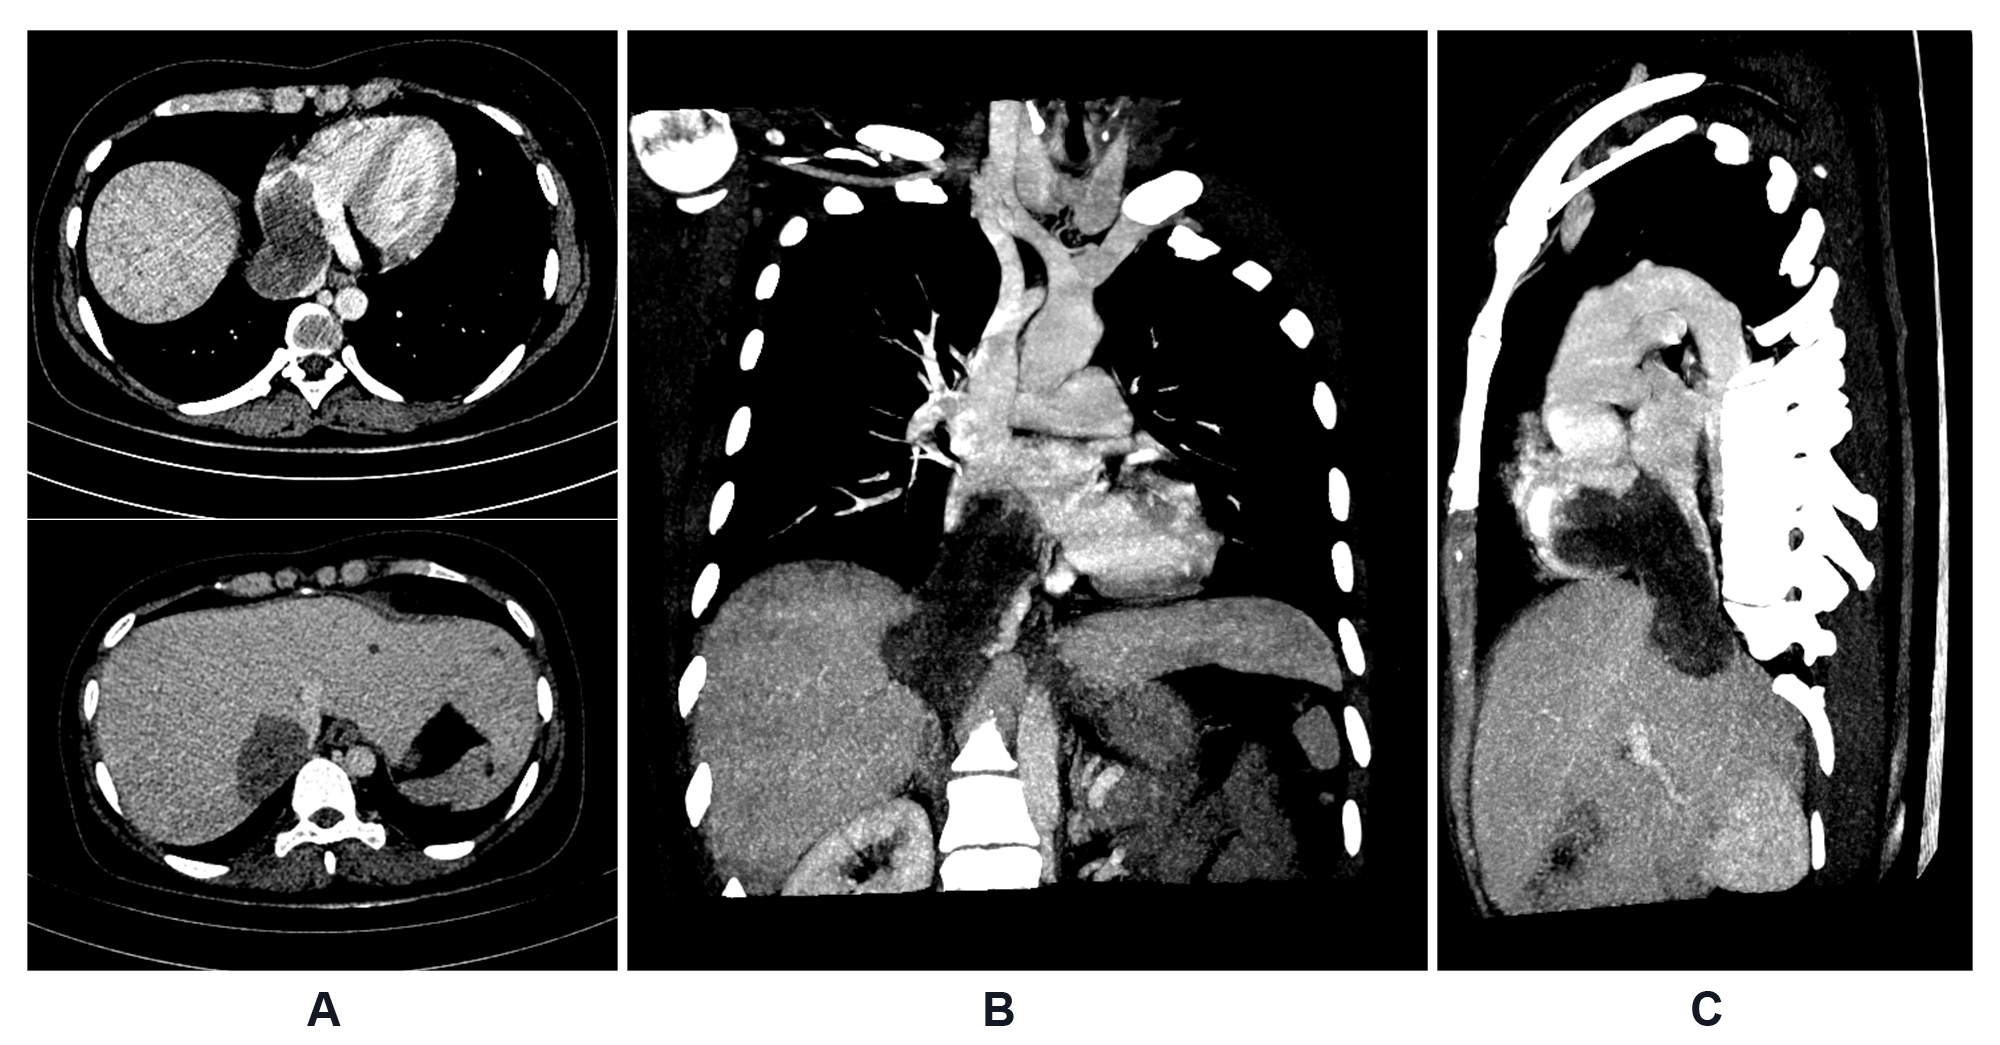

A transthoracic echocardiogram revealed a large mass occupying almost the entire right atrium, extending into the inferior vena cava. A CT scan showed a large, low attenuation, and minimally enhanced mass extending from the right atrium into the inferior vena cava and right hepatic vein, possibly invading segments VII-VIII of the liver (Figure 1). Abdominal CT and MR images revealed multiple degenerating uterine fibroids, bilateral dilated uterine tubes, and mild right hydronephrosis (Figure 2).